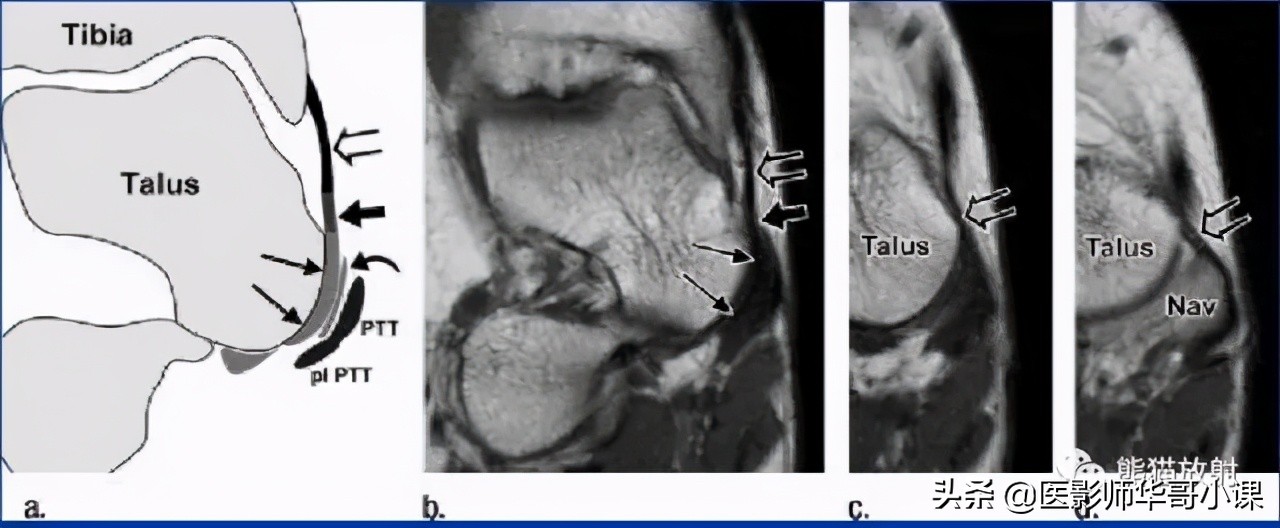

↓ 胫舟韧带

↓ 胫跟韧带

↓ 胫距前韧带

↓ 胫距后韧带